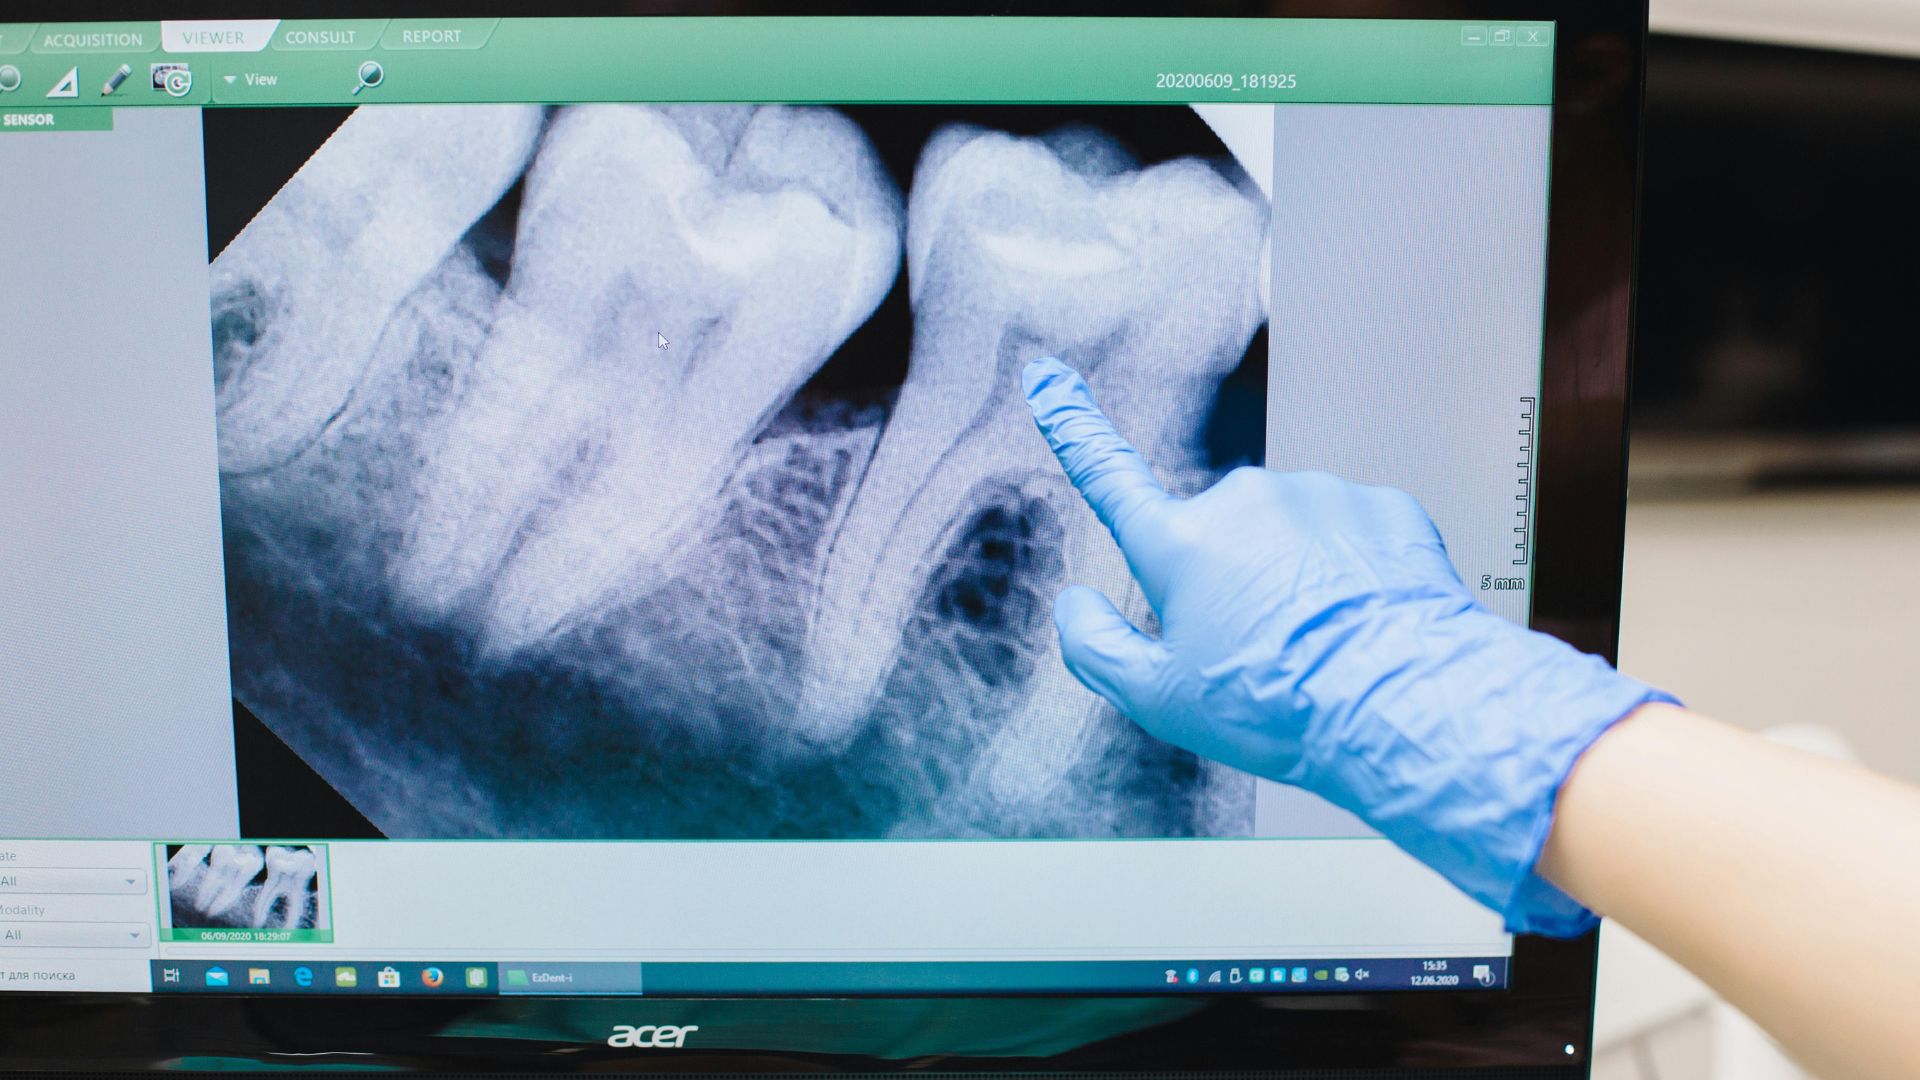

- Chụp X-quang răng: Xem lỗ sâu, tổn thương chân răng, hoặc áp xe quanh chóp, giúp xác định mức độ viêm tủy và lập kế hoạch điều trị.

- Xét nghiệm máu hoặc CT (nếu cần): Kiểm tra viêm toàn thân hoặc bệnh nền (như tiểu đường) qua máu; chụp CT 3D đánh giá tổn thương xương, tủy chi tiết trong trường hợp phức tạp.